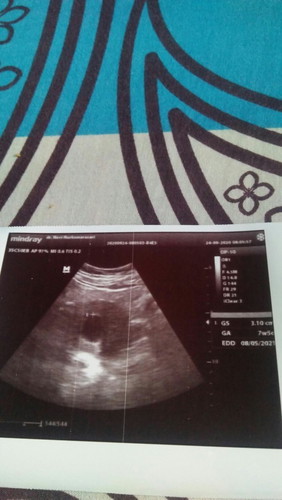

Kehamilan saya baru 7minggu,di usg katanya ada kantung bayi saja isi nya kosong..

Gimna apa bayinya tidak berkembang?